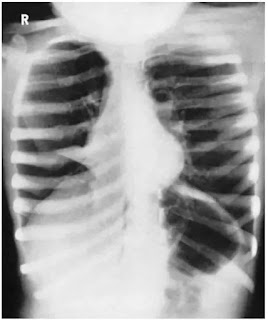

Chest lordotic x-ray in hindi

यह technique का उपयोग right middle -lobe collapse या किसी inter-lobar pleural effusion को देखने मे किया जाता हैं।

Patient को जिस प्रकार Chest PA projection में खड़ा किया जाता हैं ठीक उसी position खड़ा करते हैं । पेशेंट को bucky के किनारे को पकड़ाकर पीछे की ओर झुकाते है। इस dorsiflexion की degree अलग अलग subject के लिए अलग अलग होती है लेकिन सामान्यतः 30-40 डिग्री होती हैं।

Horizontal central ray को cassette के लम्बवत फ़िल्म के बीच देते हैं।